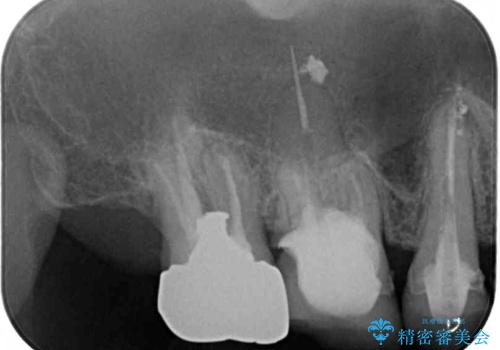

診査の結果、左側は奥歯2本、右側は1本の抜歯が必要であることが分かりました。

左側は大臼歯2本と小臼歯1本が欠損しているため、インプラント2本を治療したブリッジ、右側は中間欠損であり、前後の歯も加療が必要であったためブリッジによる補綴治療を行うこととしました。

抜歯となった歯は全て神経が抜かれた歯であり、強大な咬合力によって破折したことが原因で抜歯となりました。